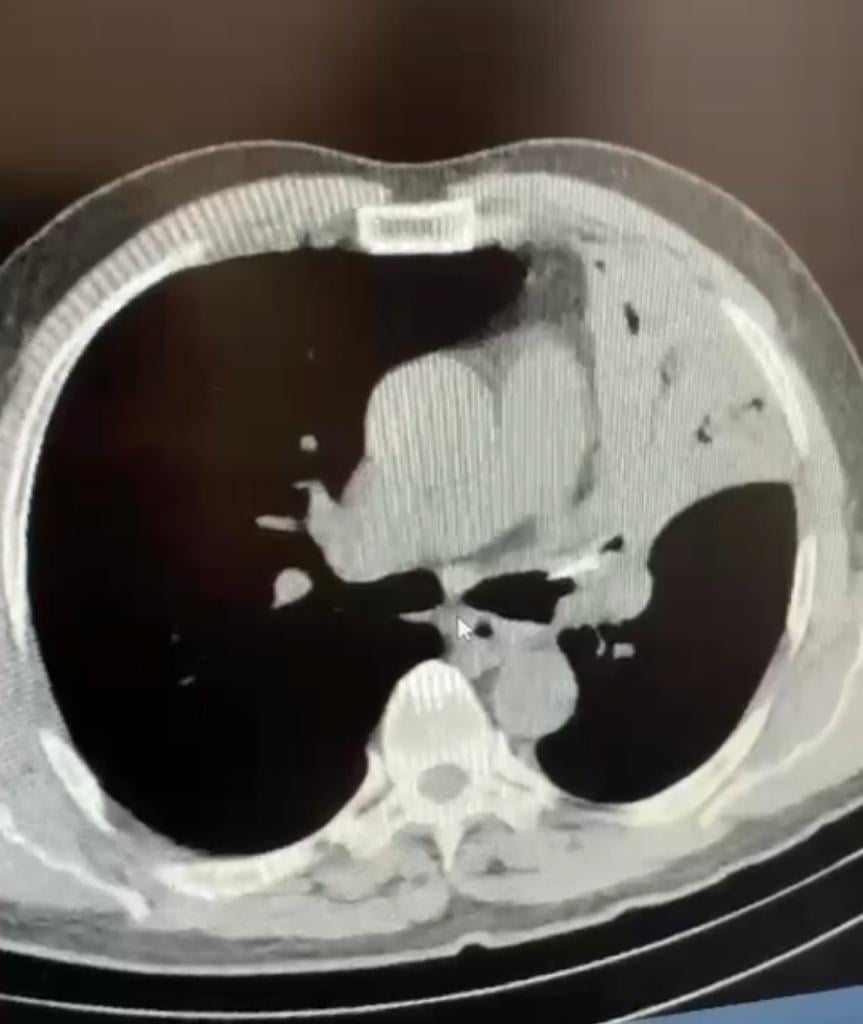

Bolu’da akciğerinde 5 yıldır lades kemiği bulunan kişi ameliyat edildi

BOLU (AA) – Bolu'da, bir kişinin akciğerinde 5 yıldır bulunan yediği tavuğun lades kemiği ameliyatla çıkarıldı.

İl Sağlık Müdürü Muhammed Emin Demirkol, sosyal medya hesabından yaptığı açıklamada, Abant İzzet Baysal Üniversitesi (AİBÜ) İzzet Baysal Eğitim ve Araştırma Hastanesi Göğüs Cerrahisi ekibinin başarılı ameliyatıyla 5 yıl boyunca sol akciğerinde lades kemiğiyle yaşamını sürdüren hastanın şifa bulduğunu belirtti.

Demirkol, 5 yıl boyunca öksürük, şiddetli ağrı, sırtında yanma şikayetleri bulunan hastaya Göğüs Cerrahisi Anabilim Dalı Başkanı Öğretim Üyesi Prof. Dr. Hacıali Kılıçgün koordinesinde Dr. Öğretim Üyesi Osman Yakşi ve Araştırma Görevlisi Dr. Muhammed Yavuz Haktanır tarafından endoskopik müdahale yapıldığını kaydetti.

İl Sağlık Müdürü Demirkol, ekibin başarılı müdahalesiyle akciğerinden tavuk kemiği çıkarılan hastanın sağlığına kavuştuğunu ifade etti.